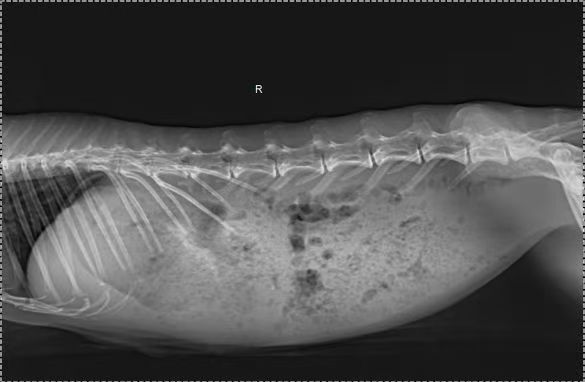

As an exotic pet specialist, our first step was to perform a routine examination. Blood tests and X-rays revealed that the rabbit had no dental issues and no other major organ problems. Despite symptomatic treatment, the rabbit’s condition did not improve. Based on the findings, we suspected that the rabbit’s gastrointestinal motility might be delayed, leading to indigestion.